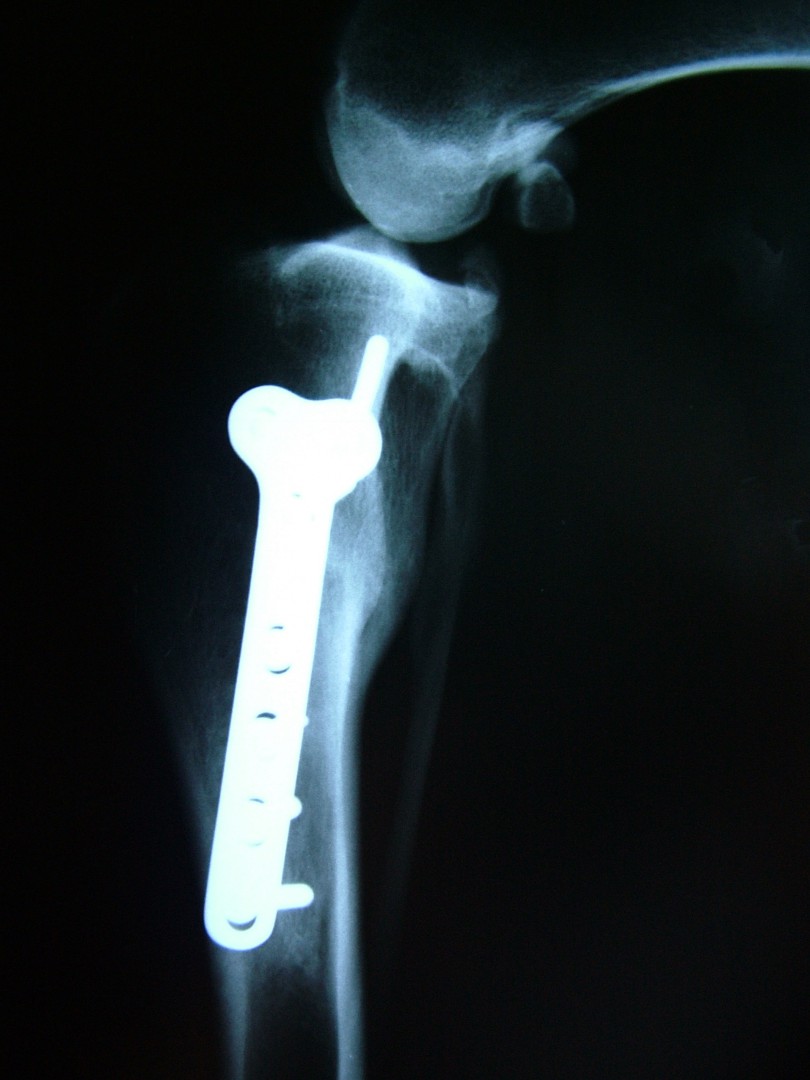

Az utóbbi 25 év egyik legnagyobb előrelépését jelentette a kereszteződőszalag szakadás műtéti megoldásában az amerikai származású Barclay Slocum által kifejlesztett műtéttechnika, mely alapja a szakadásra hajlamosító tényezők és a szalagra ható fizikai erők vizsgálata. Barclay Slocum olyan műtéti technikát dolgozott ki, mellyel a térdízületet az elülső kereszteződőszalagra ható erőkhöz igazítja. Vizsgálatai alapján a sípcsont ízületi felszínének meredeksége (tibia plató szög, tibial plateau angle, TPA) és az elülső kersztezőszalag szakadása között egyértelmű összefüggés mutatható ki. A műtét alapja, hogy a sípcsont ízületi felszínét a sípcsontból kivágott ék, majd azt követő lemezes osteosynthesis segítségével a sípcsont hossztengelyére megközelítőleg merőlegesre állítja be, csökkentve ezáltal a szalagra ható erőket (cranial wedge tibial osteotomy, CWTO).Ezt a technikát továbbfejlesztette: a sípcsonti ízületi felszín szögellésének korrekcióját egy speciális félkör alakú fűrész segítségével, az ízületi felszínt is magába foglaló sípcsonti részlet kivágásával, elforgatásával és rögzítésével oldatta meg (tibial plateau leveling osteotomy, TPLO).